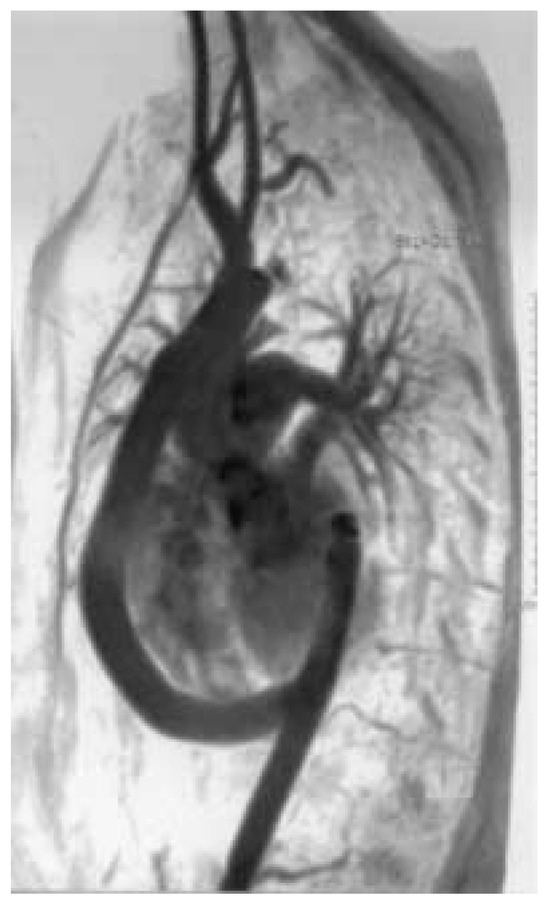

Une patiente de 31 ans souffrant d’une cardiopathie congénitale consulte car elle souhaite une grossesse [...]